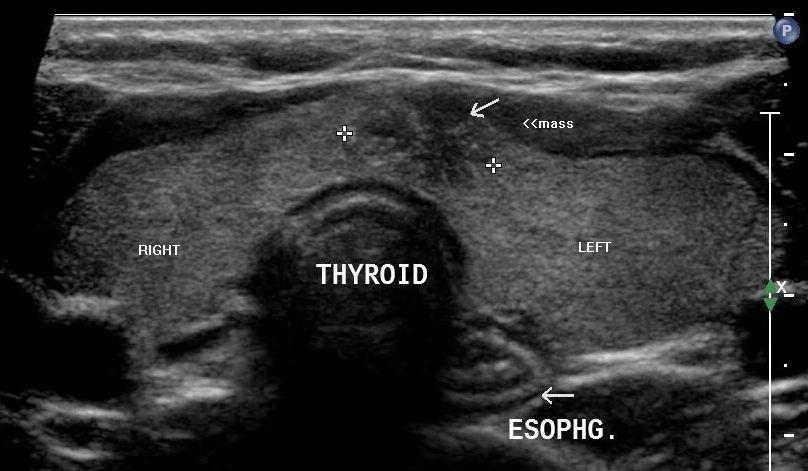

Διαγνωστικά κέντρα Καπανδρίτι, Βόρεια προάστια. Ακτινολογικό κέντρο Καπαδρίτι

Ακτινολογικό ιατρείο, ακτινολόγος Καπανδρίτι